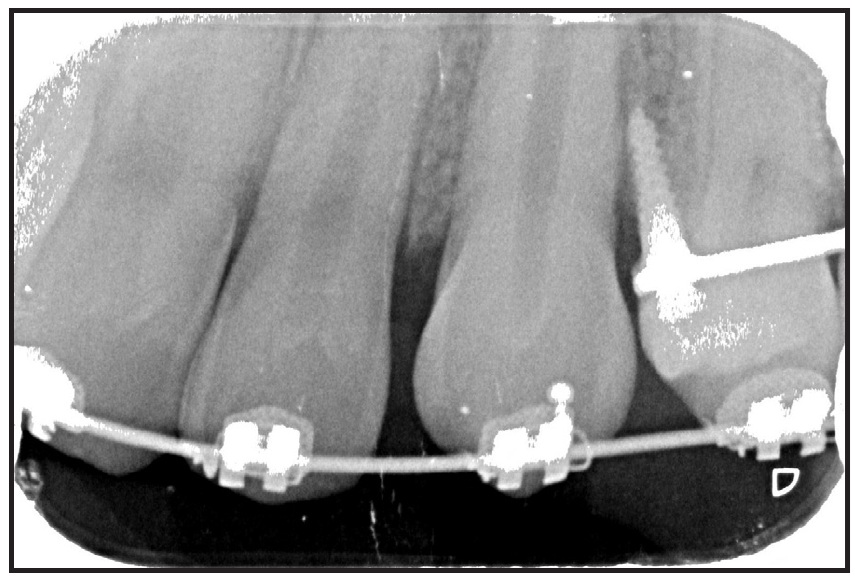

Preadjusted .022" × .028" brackets*** were placed in the upper arch, and an .014" nickel titanium archwire was used to correct the upper incisor inclination and the scissor bite (Fig. 2). After five months of treatment, a Herbst appliance with four 1.4mm × 6mm TADs† (H4T) was placed (Fig. 3). In the lower arch, one miniscrew was inserted between the right first permanent molar and second premolar and the other between the left first and second premolars. Auxiliary buttons were bonded to the buccal surfaces of the canines, and elastic chains were attached to the miniscrews to retrocline the lower incisors and promote mandibular protraction. In the upper arch, a miniscrew was inserted between the first and second premolars on each side, and elastic chains were attached between the miniscrews and an .018" × .022" stainless steel archwire for vertical control.

Fig. 4 Failed upper left TAD replaced after 11 days with TAD between canine and first premolar.